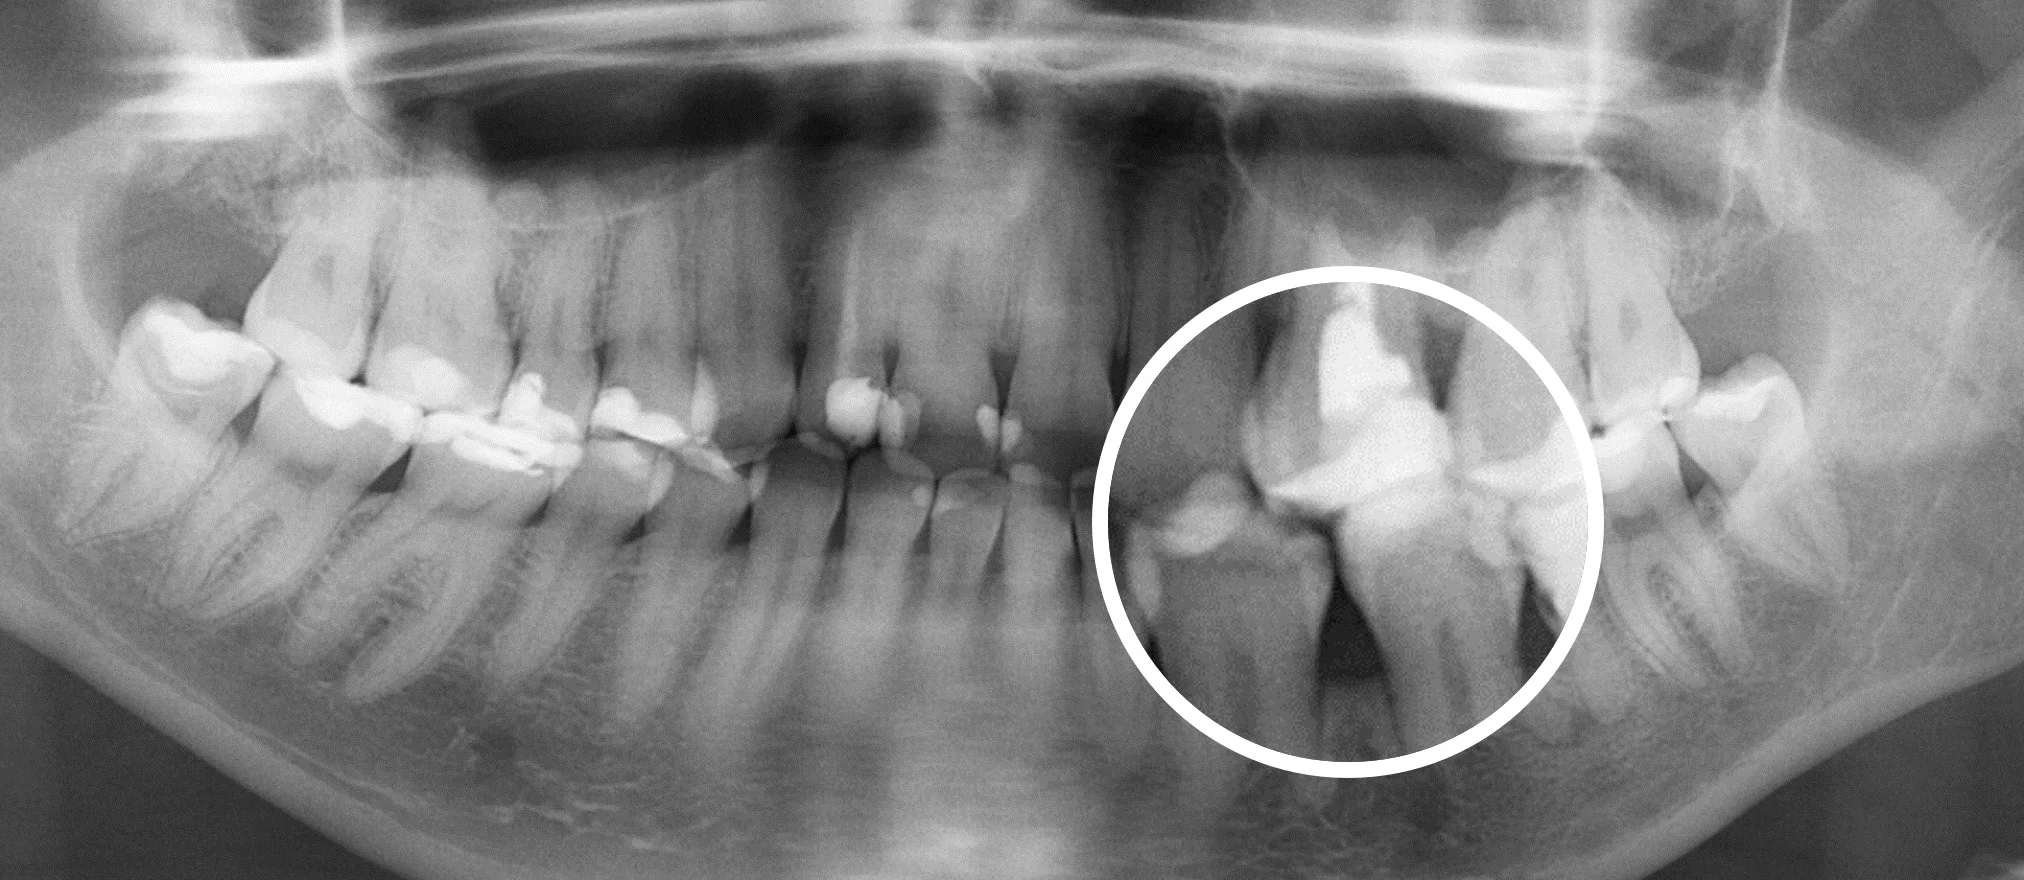

Еще 10 лет назад для того, чтобы провести диагностику зубов стоматологи использовали прицельные R-снимки и ОПГ снимки. Это снимки, которые делаются в 2D формате. Единственное, что врач мог делать с данным снимком, это приближать и удалять изображение.

На смену 2D снимкам пришли КТ снимки (компьютерная томография], которые в обиходе называют 3D снимками —новый уровень диагностики.

Сравнение 2D и 3D снимков

3D снимки — это новый уровень диагностики. Но при их появлении возникла достаточно большая сложность.

Дело в том, что 3D снимки гораздо более информативны, чем 2D снимки, но на их чтение требуется гораздо больше времени и более высокая квалификация стоматолога, это гораздо более трудоемкий процесс.

Далеко не каждый стоматолог, умеет правильно читать КТ снимки, для этого требуется отдельное обучение. Также стоматологам не хватало времени выделяемого на прием, чтобы проанализировать каждый зуб.

Что привело к тому, что комплексность диагностики начала страдать. Врачи успевали проанализировать только 1-2 зуба за прием.